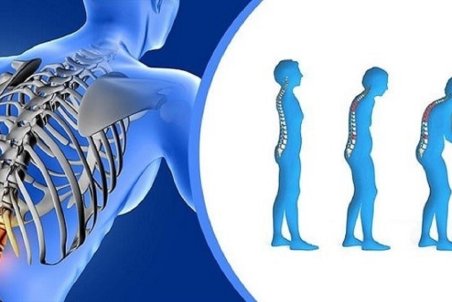

یکی از علل مهم مرگ و میر در سراسر دنیا پوکی استخوان است. استخوان بافت زندهای است که مدام در حال تخریب و بازسازی است اما معمولا از سن 35 تا 40 سالگی به بعد جذب کلسیم کم شده و به علت برداشت کلسیم از استخوان، پوکی استخوان شروع میشود و به دنبال آن افزایش احتمال

دردی خاموش به نام "آستئوپروز"

بیماری پوکی استخوان یا «آستئوپروز» معروف به درد خاموش، عارضهای است که در آن، تراکم سلولهای استخوانی کم و از قدرت طبیعی آن کاسته میشود و در این حالت استخوان شکننده خواهد شد و احتمال شکستگی حتی بر اثر ضربات کوچک افزایش مییابد.

با افزایش سن استخوانها نحیفتر و ضعیفتر شده و تراکم خود را از دست میدهند و از همین رو با گذشت زمان آسیبپذیرتر میشوند.